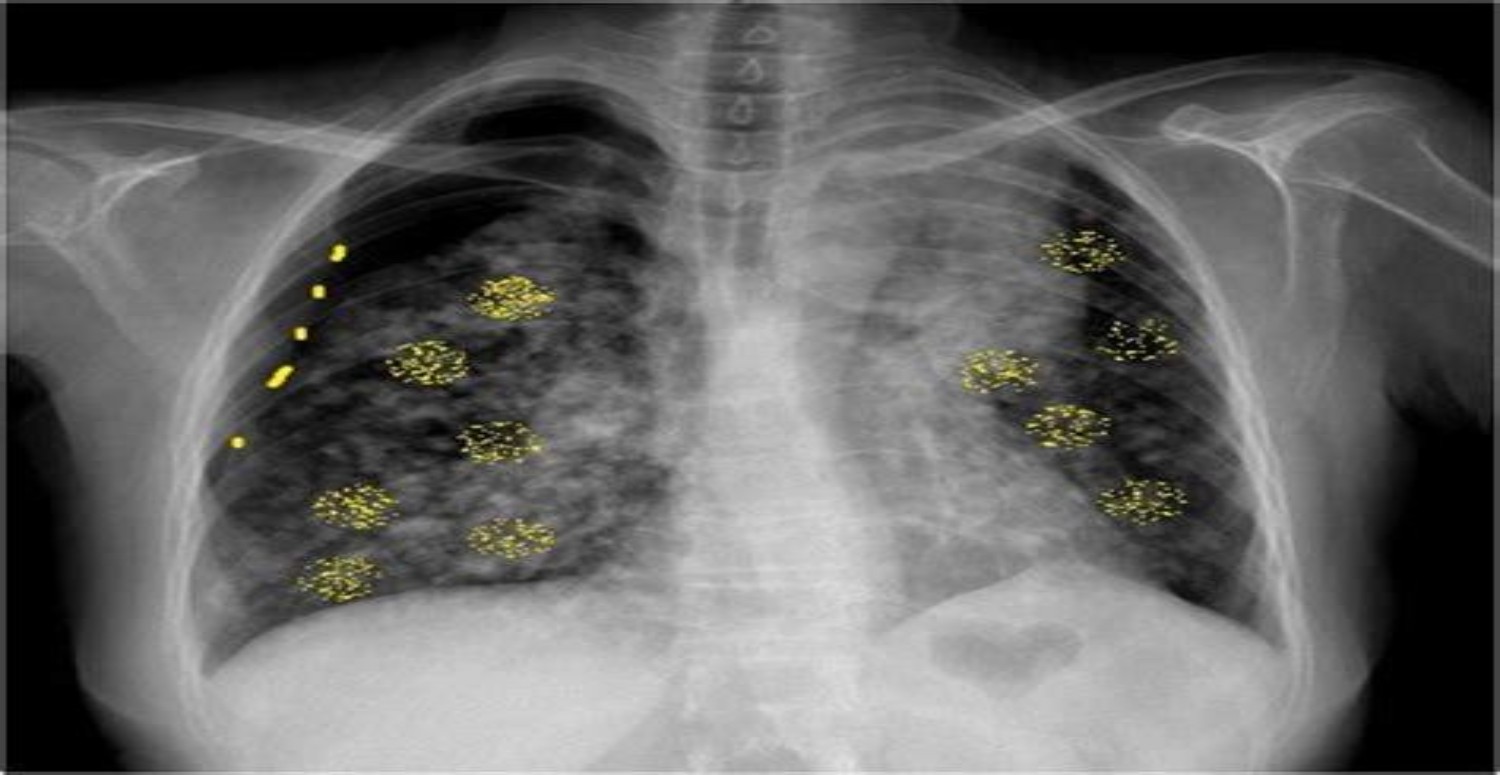

Bu belirtilerden bir veya birkaçından yakınan kişilerin vakit kaybetmeden bir sağlık kuruluşuna başvurması gerekiyor ve en azından bir akciğer filmi çektirmesi gerekiyor.

Ayrıca, akciğer kanserinden korunmak için 50 yaş ve üzeri, halen sigara içen veya daha önce uzun süreli sigara içme geçmişi olan kişilerin düşük doz radyasyona maruz kalınarak yapılan bilgisayarlı tomografi taraması yaptırmasını öneriliyor.